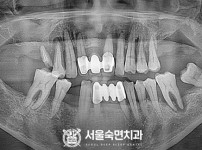

임플란트-전후사진1

치과를-선택할-때-꼭-확인하세요-서울숙면치과-임플란트-전후사진